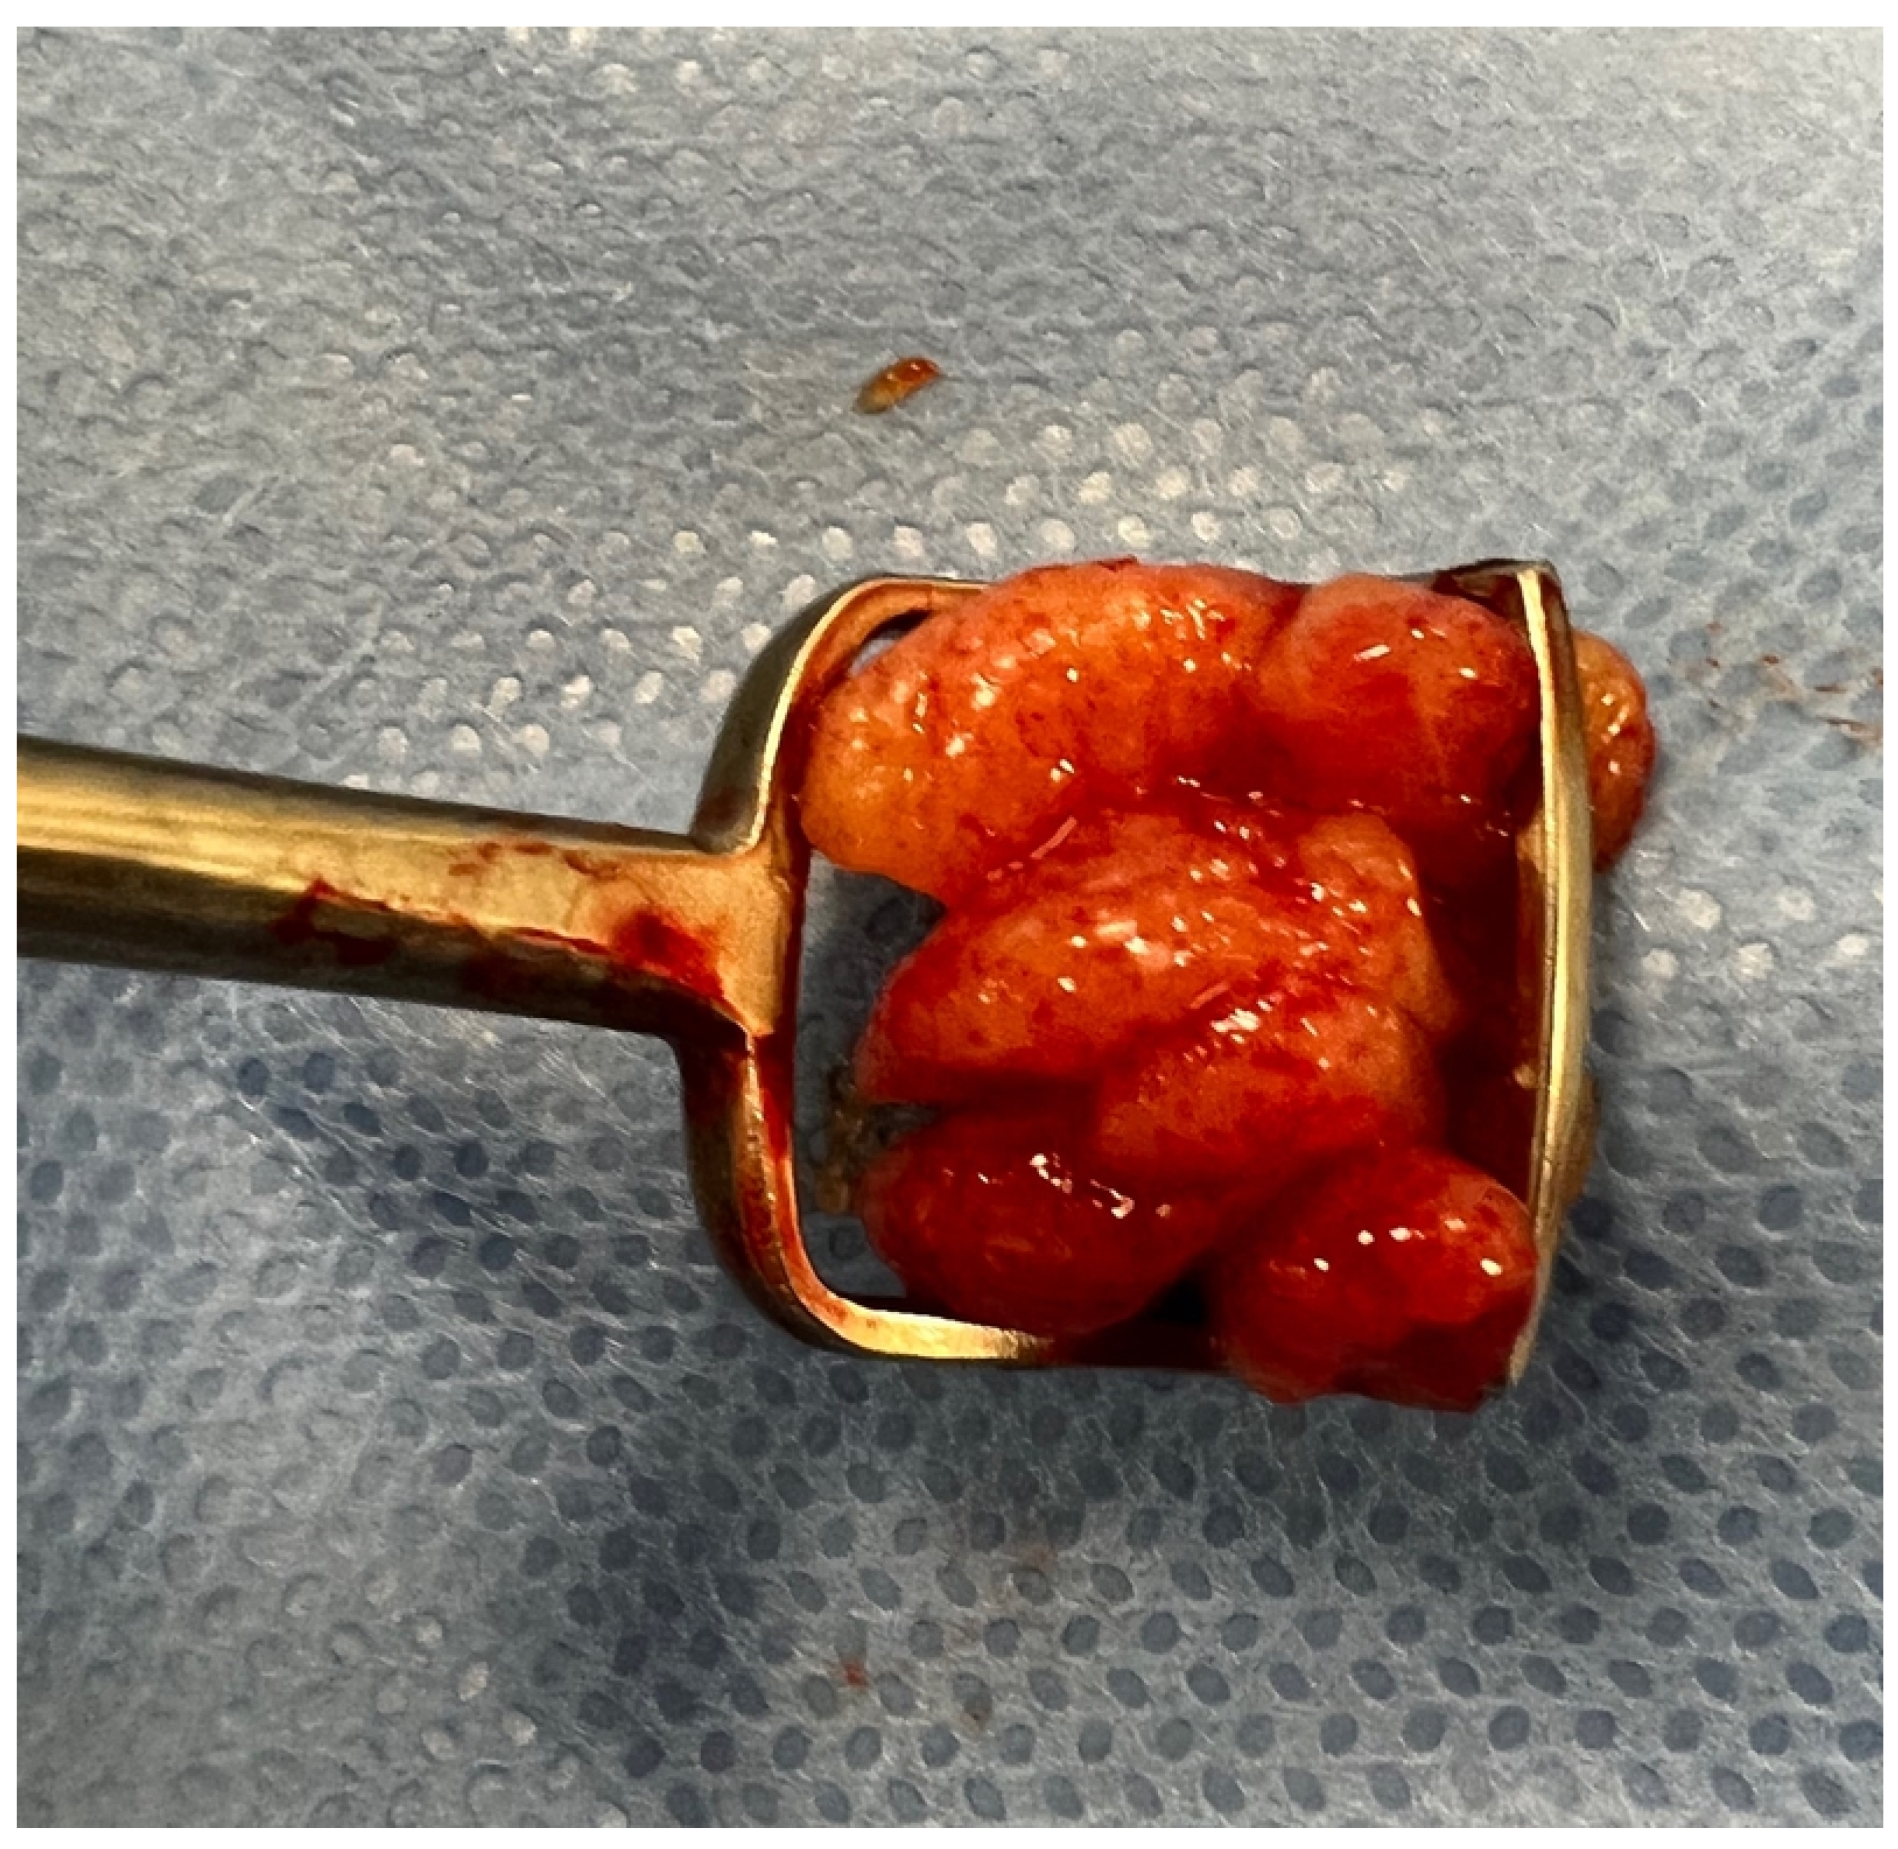

2.5. Surgery